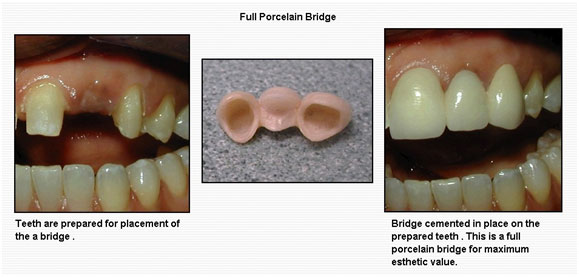

Restoring Smiles with the Benefits of Crowns & Bridges at Altamash Dental Clinic

Your healthy, confident smile is more than about looks—it influences your speech, chewing function, and entire oral health.